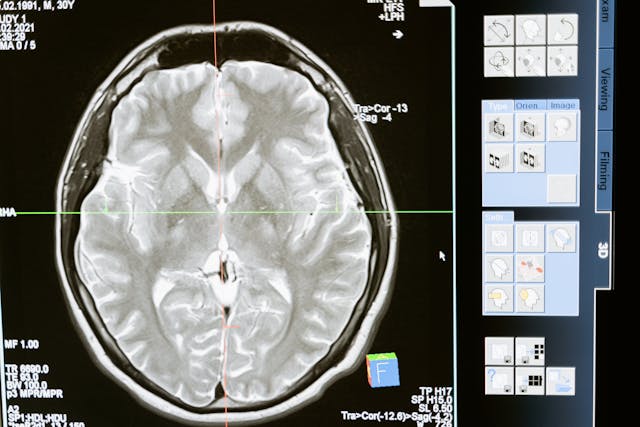

Your brain can generate a full world without outside input. Dreams prove it each night. Hallucinations show it in waking life. The NHS defines them with clinical clarity. “Hallucinations are where you hear, see, smell, taste, or feel things that appear to be real but only exist in your mind.” These experiences can appear with psychosis, neurological illness, sleep deprivation, grief, or certain drugs. They can also occur with sensory loss, where the brain fills gaps. The important truth is simple. Perception is an active construction. The brain combines signals, expectations, and attention into a scene. When the balance shifts, the brain can produce vivid images or voices that have no external source. In rare syndromes, belief can also detach from physical evidence. Cotard’s syndrome is one example.

A clinical review by S. Grover and colleagues described it as a condition “in which the patient denies the existence of one’s own body.” That denial can lead to self-neglect, because the person rejects basic needs. Hallucinations can also be brief and situational. Some people see shapes during a fever. Some hear a voice when falling asleep or waking. Clinicians look at timing, stressors, and safety risks. They also look for medical causes that need urgent care. This separates a transient symptom from a dangerous spiral. The larger lesson remains. The brain can run its perception engine in standalone mode. When it does, the output can be convincing enough to guide behaviour.